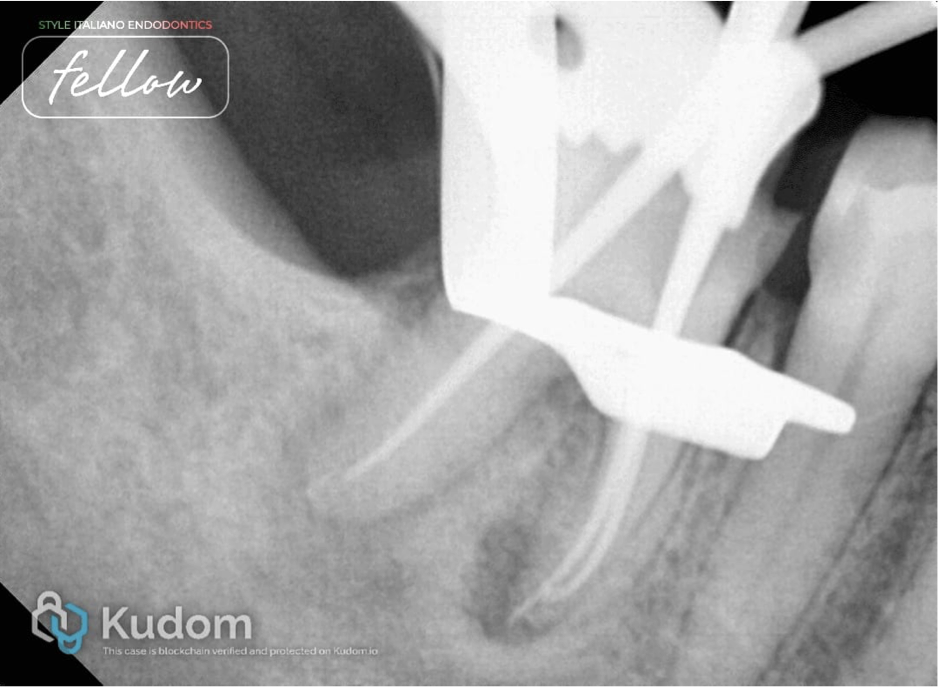

Fig. 6

X-ray taken after completion of the endodontic treatment. It shows healing in both roots. The periapical lesion decreased in size in the mesial and distal root. New bone formation has taken place in the previously lesioned periapical area.